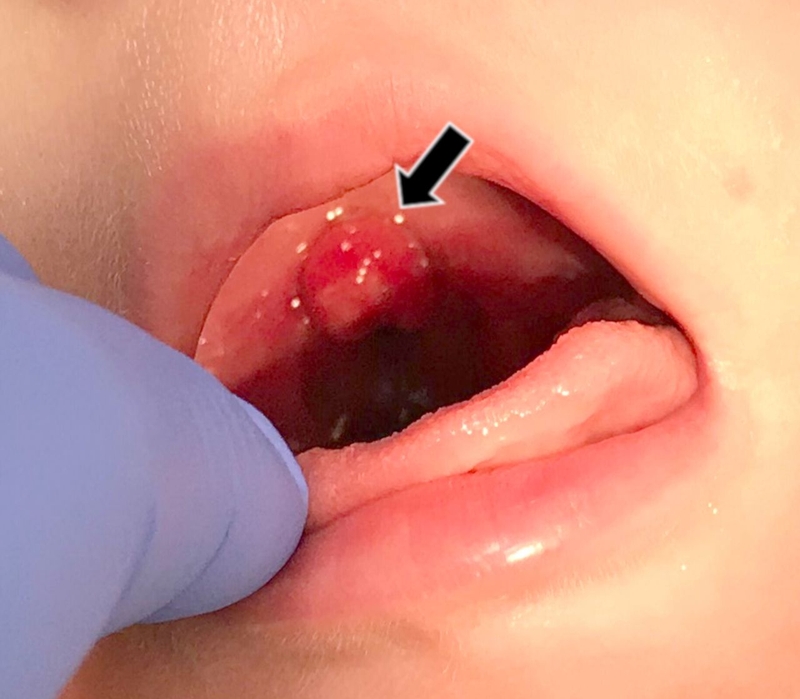

Sưng lưỡi gà có thể là dấu hiệu của viêm lưỡi gà. Tình trạng này gây khó chịu cho người bệnh nhưng thường chỉ là tạm thời. Tuy nhiên, nếu để bệnh tiến triển nặng, chúng có thể ảnh hưởng đến khả năng nuốt của bạn. Trong một số ít trường hợp, nó có thể gây khó thở. Có nhiều nguyên nhân có thể gây ra sưng lưỡi gà và đôi khi bệnh tự khỏi, trong khi những trường hợp khác cần phải điều trị. Vì vậy, cần nắm được những nguyên nhân này để chủ động trong việc phòng tránh.

Một số bệnh nhiễm trùng có thể gây kích ứng lưỡi gà và gây sưng tấy, những loại nhiễm trùng này bao gồm cảm cúm, viêm thanh quản, viêm amidan nặng, nấm miệng, bệnh nhân suy giảm miễn dịch,...

Tổn thương ở lưỡi gà có thể do bệnh tật hoặc phẫu thuật. Nôn mửa quá mức và trào ngược dạ dày cũng có thể gây viêm họng và sưng lưỡi gà.